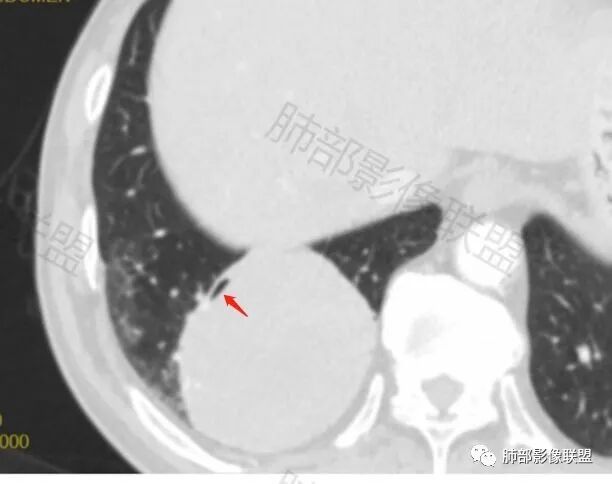

男性,62,胆结石入院胸部CT偶然发现占位。肿标稍增高,右肺下叶胸膜下肿块,边缘尚清,密度较均匀,增强明显强化,血管贴边,空气新月征?静脉期可见低强化区,首先考虑PSP,鉴别肉瘤样癌及神经内分泌肿瘤

右肺下叶肿块,呈外带大内带小的椭圆形改变(内带受支气管及血管挤压原因),边缘光滑,无分叶毛刺,支气管受压,增强后,均匀延迟强化,动脉期见血管贴边,静脉期内部瘤样血管强化区,相邻胸膜无侵犯,纵隔无淋巴结肿大,符合PSP,不鉴别。

肿块位于周围(起自细支气管呼吸道上皮),均匀膨胀生长(符合良性的生长特点),病灶内部大部分密度较均匀,部分小低密度不强化区(囊变),增强强化较明显,边缘血管增粗贴边,临近支气管受压,支持PSP。

但是这条血管需要交代一下:

如果这是同一根肺动脉,支持PSP